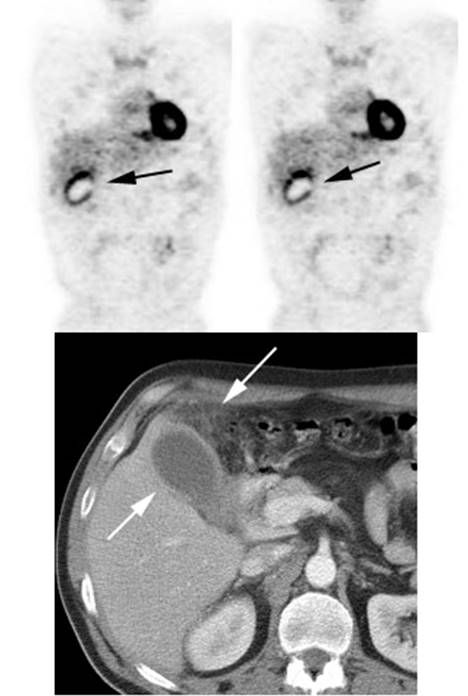

Figure 28 - Inflammation: The image below

demonstrates ring-like increased tracer activity surrounding the gallbladder in

a patient with cholecysitis (black arrows). Note the

gallbladder wall thickening and adjacent inflammatory changes seen on the

patient's CT